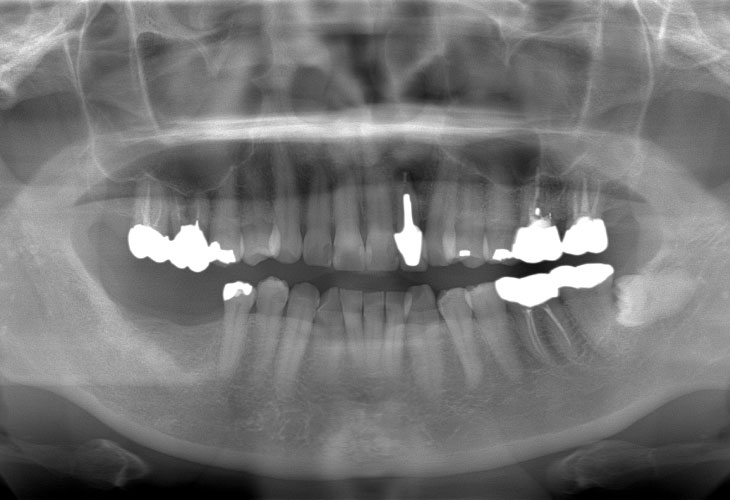

下顎臼歯部インプラント治療(2本)

治療内容 インプラント(右下6・7)

インプラント: 4ヶ月/6回

定期的なメインテナンスを行わない場合、インプラントが脱落する可能性があります。被せ物は経年的な劣化で欠ける可能性があります。